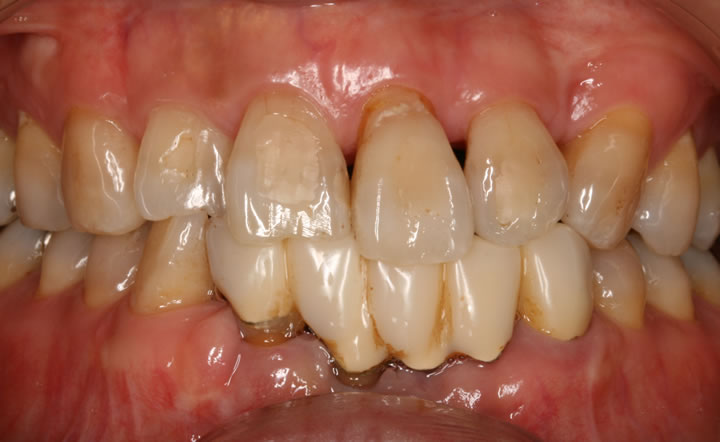

治療前

初診30代女性の初診時の写真です。前の歯をきれいにしたいと来院されました。

上の前歯の拡大写真です。